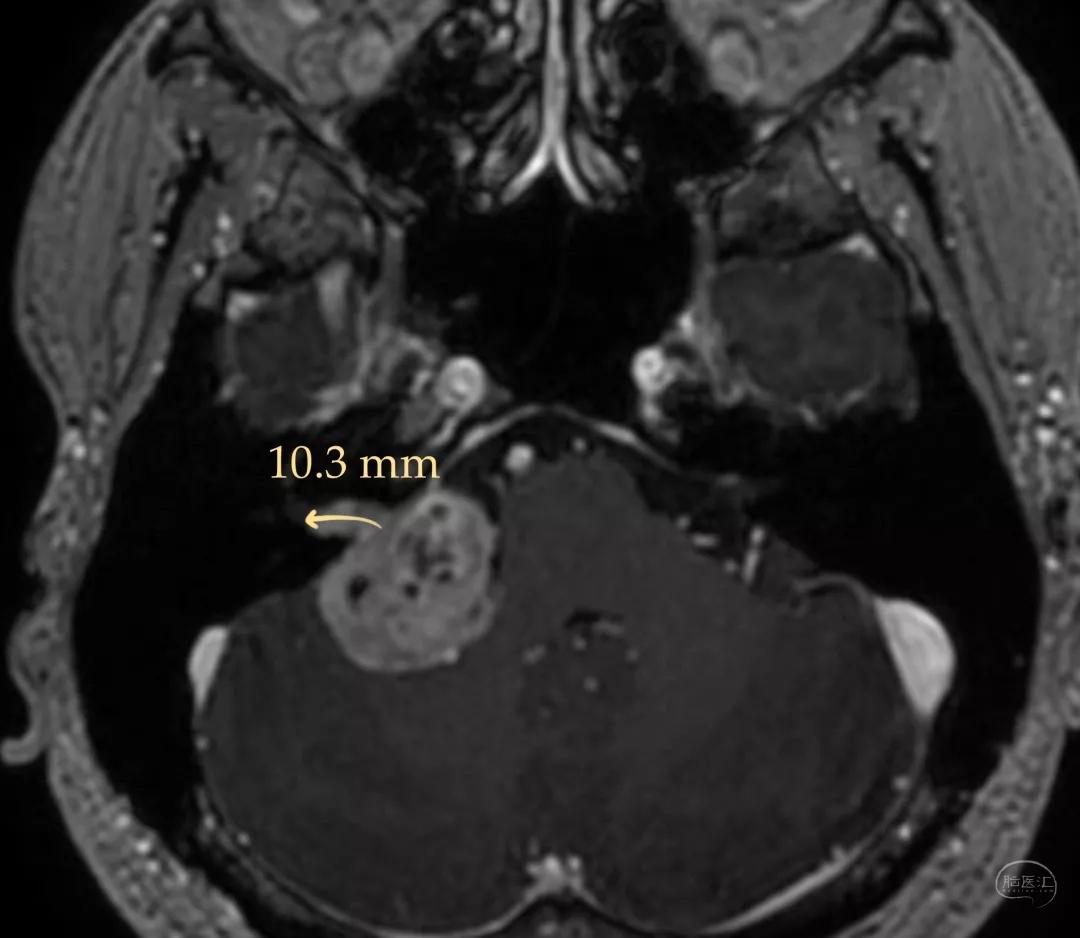

# CASE2 #

患者:男, 31y

右耳耳鸣八年

右耳听力下降半年

核磁共振检查发现右侧桥小脑角区占位

脑干和小脑受压明显

肿瘤最大直径-约3.1cm

术前影像资料

肿瘤长入内听道内较深-10.3mm

肿瘤压迫脑干